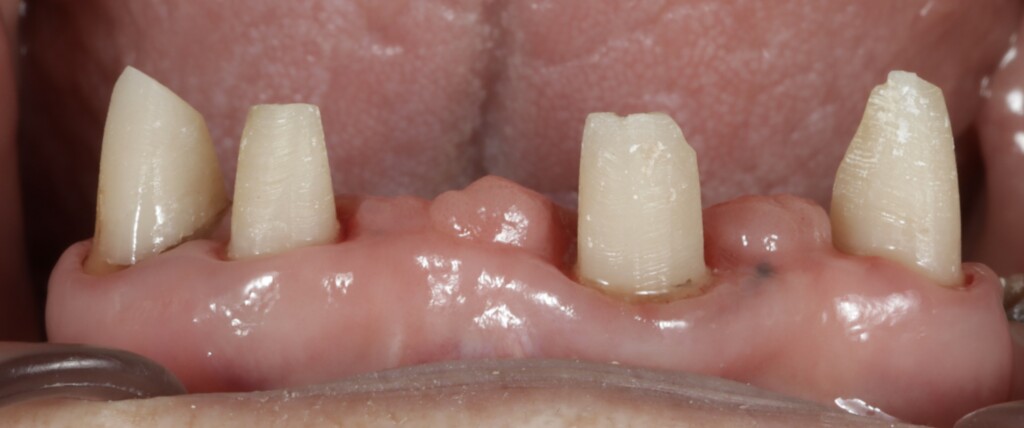

まずは仮歯と仮の入れ歯を用いて、乱れていた見た目や噛み合わせの平面を整えました。そのうえで、その状態が実際にお口の中で無理なく機能するか、違和感なく順応できるかを確認し、残っている歯の状態を評価しました。さらに、ブリッジやクラウンによる修復が可能かどうかについても、慎重に判断を行いました。残っている歯はいずれも神経の処置がされている歯でしたが、根管内の状態に問題が認められたため、再度根管治療を行っています。具体的には、仮歯を外して根管治療を行い、治療後に土台を立て、再び仮歯を仮止めで装着する、という工程を繰り返し行いました。

仮歯を外した状態(上顎前歯は土台が立っている)

上顎前歯部は健全歯質が縁上にほとんどない

右上奥歯も健全歯質が少ない

上顎の残っている歯は、これまでブリッジや被せもので連結されていたため分かりにくい状態でしたが、詳しく評価を行ったところ、左上の犬歯(糸切り歯)を除き、いずれの歯にも動揺が認められました。また、骨に埋まっている部分(支持組織)も少なく、歯を支える力が低下している状態でした。この点については、治療開始前の検査の段階である程度予測はできていましたが、実際には歯ぐきより上に十分な健全歯質も残っていない状況でした。このような歯に対して、ブリッジやクラウンのように歯へ大きな負担がかかる治療方法を選択し、さらに部分入れ歯の留め金をかける設計とした場合、負担が集中し、状態の悪化を招く可能性があります。そのため今回は、支える力が低下している歯への負担をできる限り抑える設計として、磁性アタッチメントを用いた入れ歯をご提案しました。